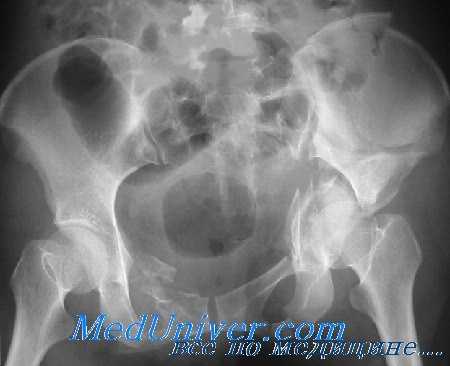

Переломы вертлужной впадины могут оказаться трудными для выявления на первичных рентгенограммах таза в прямой проекции. При подозрении на эти повреждения важно тщательно изучить нормальные анатомические ориентиры, окружающие вертлужную впадину и изображенные на рис. 176. При подозрении на перелом вертлужной впадины следует сделать рентгеновские снимки в следующих проекциях:

Задняя опора и передняя губа лучше просматриваются на снимке в наружной косой проекции под углом 45°, в то время как задняя губа и передняя опора — на снимке во внутренней косой проекции под углом 45°. Кроме того, переломы заднего столба будут искажать подвздошно-седалищную линию, в то время как переломы передней опоры приведут к деформации подвздошно-лонной линии. Центральные переломы вертлужной впадины лучше выявляются на задней косой проекции. Некоторые виды переломов таза нередко сочетаются с переломами вертлужной впадины, которые не всегда легко выявить рентгенологически.

Прямая проекция тазобедренного сустава (вертлужной впадины). У больного с подозрением на перелом следует тщательно осмотреть эти линии. При скрытом переломе может наблюдаться смещение только одной из этих линий